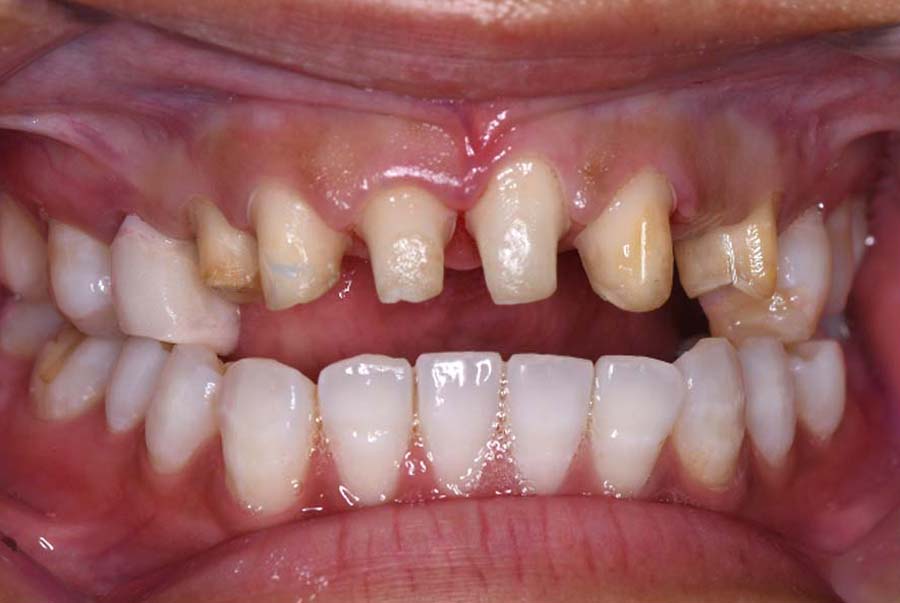

噛み合わせ治療の症例24

スプリント使用後、

補綴治療をした症例

| 治療内容 | ①スプリントを装着 ②副子を装着 ③2024年4月 口腔内反映開始 ④副子を入れた状態の所まで咬合を挙上 (バイトアップ) ⑤2024年5月 上顎前歯部8本へ仮歯(TEK) を装着 |